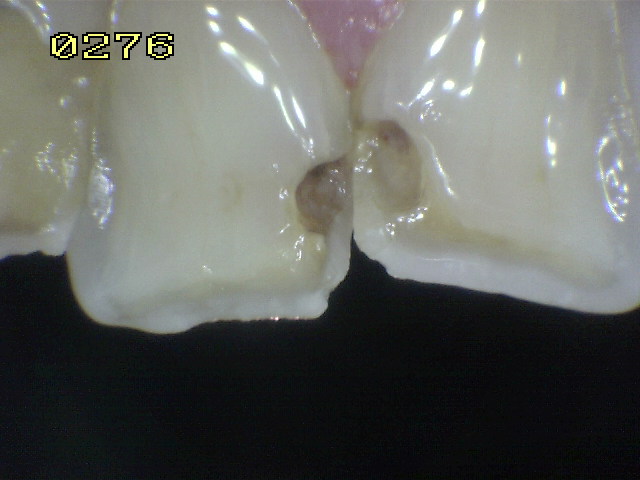

Código 2

Código 1